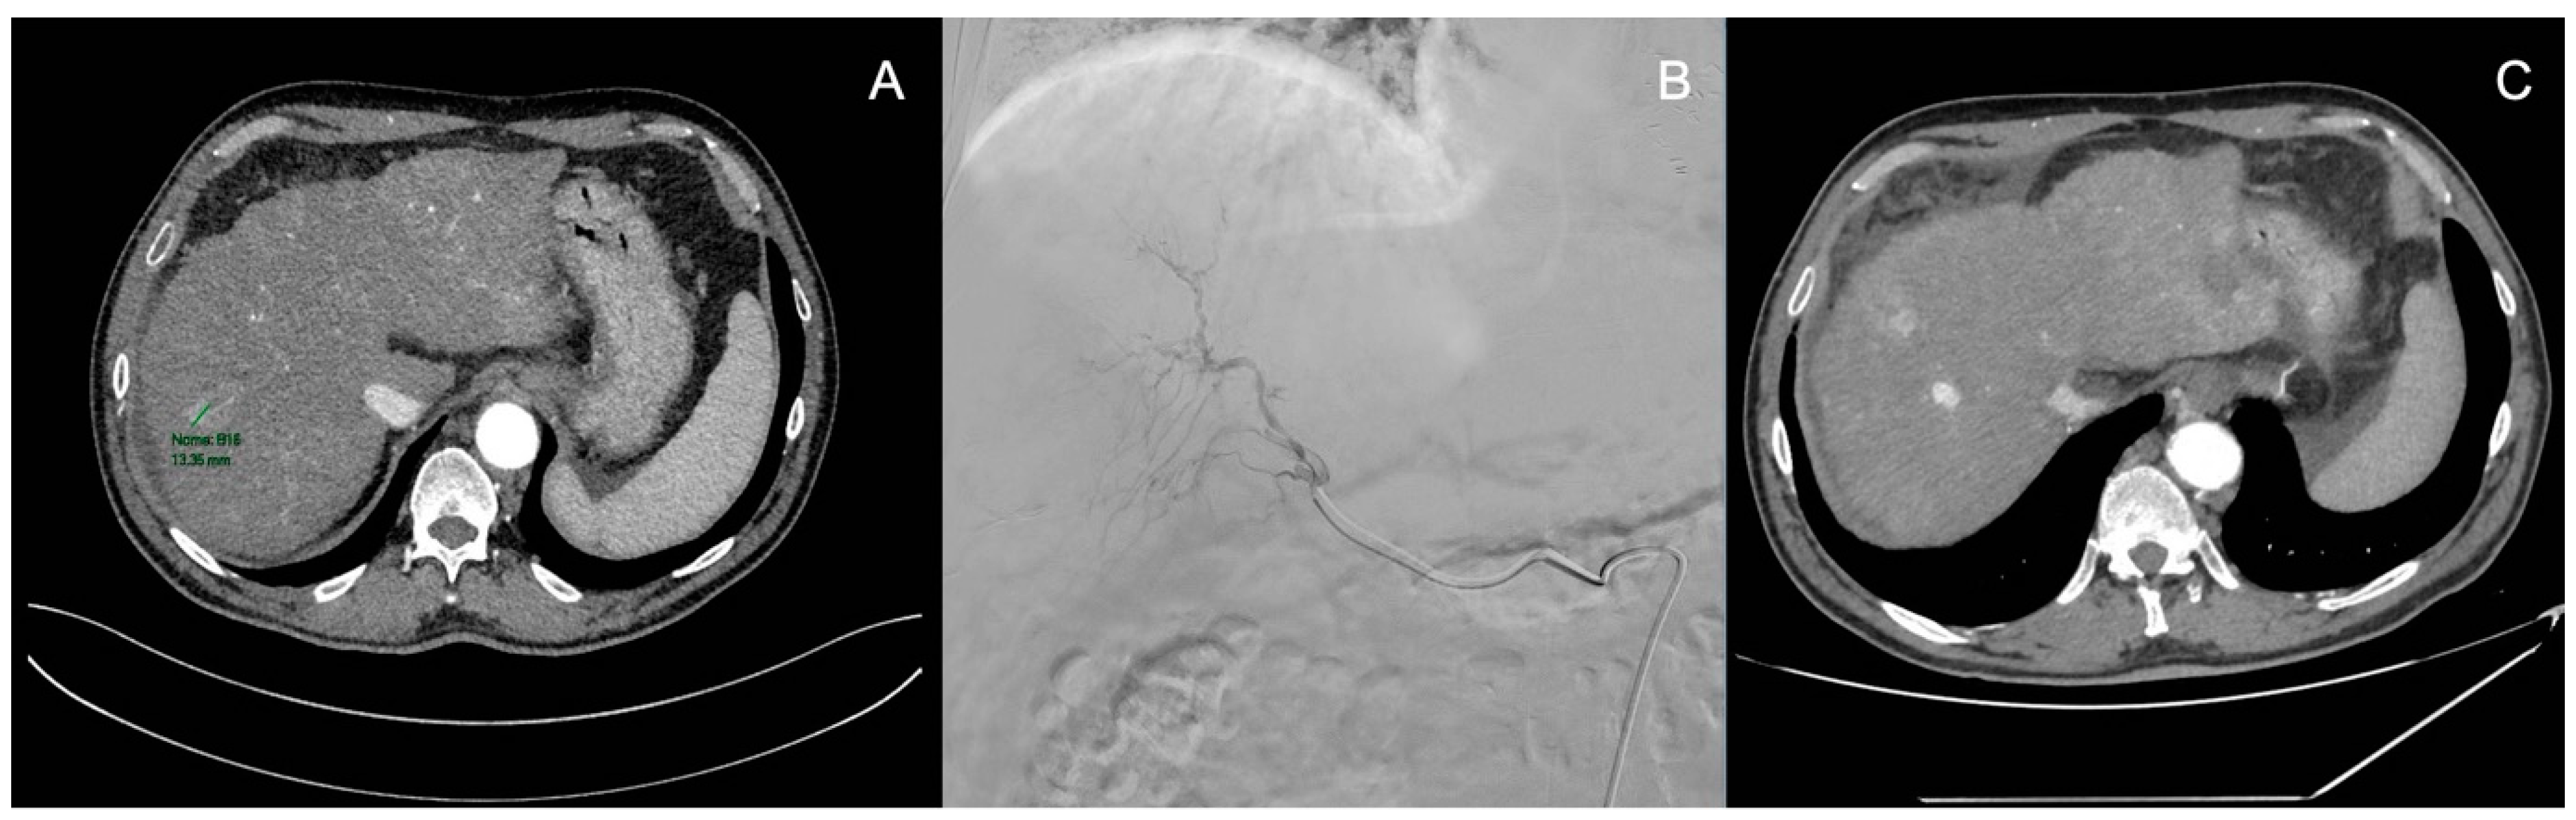

3.3. Transarterial Radioembolization (TARE)

4.2. Transarterial Chemoembolization (TACE)